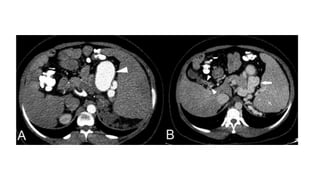

• The modified caudate-to-right lobe ratio with the right portal vein as

the lateral border and an abnormal value >0.9 had higher accuracy.

• The right posterior hepatic notch sign indicates a sharp indentation

along the right posteromedial surface of the liver between the

hypertrophied caudate and the atrophic right posterior segment.

• Widened porta hepatis anterior to the main portal vein at the hilum is

also associated with cirrhosis

• #13 Axial venous phase images of contrast enhanced CT (A) right posterior hepatic notch sign and (B) volume redistribution with widened porta hepatis.